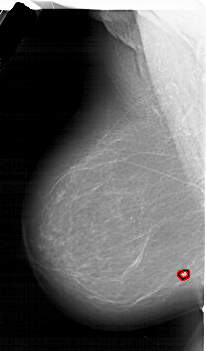

A_1639_1.LEFT_CC

LEFT_CC LINES 6856 PIXELS_PER_LINE 3901 BITS_PER_PIXEL 12 RESOLUTION 43.5 OVERLAY

FILE: A_1639_1.LEFT_CC.OVERLAY

TOTAL_ABNORMALITIES 1

ABNORMALITY 1

LESION_TYPE MASS SHAPE IRREGULAR MARGINS ILL_DEFINED

ASSESSMENT 4

SUBTLETY 2

PATHOLOGY MALIGNANT

TOTAL_OUTLINES 1